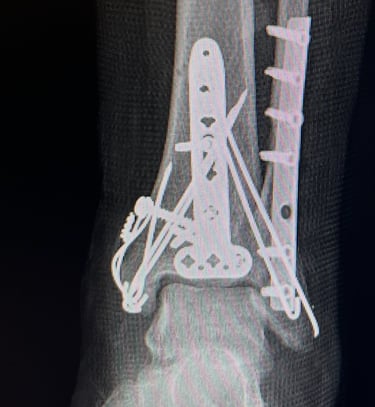

Mi occupo del trattamento traumatico sia in forma conservativa sia chirurgica. Tratto fratture, lussazioni, lesioni dei legamenti e dei tendini, con l’obiettivo di ripristinare la funzionalità articolare, ridurre il dolore e favorire un rapido ritorno alle attività quotidiane e sportive.